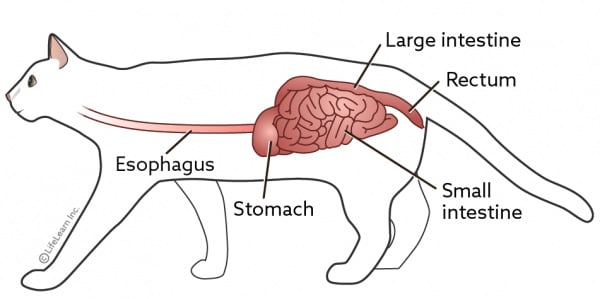

Bowel Obstruction Intestinal Blockage in cats PDSA top, Gastrointestinal Foreign Bodies FB In Dogs Cats top, Intestinal obstruction in cats Veterinarian Karlsruhe Small Animal Center Arndt top, Please read my baby is suffering from blocked intestines. guide me what to do. r CATHELP top, Intestinal Blockage in Cats PetMD top, Constipation in Cats VCA Animal Hospitals top, Please read my baby is suffering from blocked intestines. guide me what to do. r CATHELP top, What To Do If Your Cat Swallows a String top, Burmese and pica Ace and his intestinal obstruction Perth Cat Hospital top, Imaging Intestinal Obstruction Clinician s Brief top, Arizona Veterinary Emergency Critical Care Center Gilbert AZ Pets can be curious and sometimes that leads to swallowing indigestible objects which can result in bowel or gastrointestinal obstruction.... top, What happened to my cat Virus caused intestinal blockage. r vet top, Cat Intestinal Blockage Surgery Cost Recovery Berkeley Vets top, Abdomen cat. Abdominal radiographs revealed marked gas distention of. Download Scientific Diagram top, Intestinal Blockage in Cats Vet Reviewed Signs Causes Treatment Catster top, Bowel Obstruction Intestinal Blockage in cats PDSA top, Intestinal Blockage Surgery For Cats Tigard Vet top, A Visual Guide to GI Obstruction on Radiographs top, Identifying Mechanical Obstruction on Radiographs MSPCA Angell top, Cat Intestinal Blockage Surgery Danbury Vet top, Bowel Obstructions in Dogs Cats Erin Vets top, Cat with Bowel or Intestinal Obstruction X ray Image or Radiography. Medical Imagery Stock Photo Image of science spine 172369032 top, Cat Intestinal Blockage Surgery Cost Recovery Farmington Hills Angel Animal Hospital top, Imaging Intestinal Obstruction Clinician s Brief top, Hairballs Can be Dangerous The Animal Medical Center top, Cat Has Hairball Why What To Do Dutch top, Cat Intestinal Blockage Surgery Cost Recovery Seattle Vets top, Vomiting in Cats What Causes It and How to Help BetterVet top, Cat Intestinal Blockages Surgery Matthews Veterinary Internal Medicine top, Cat With Bowel Or Intestinal Obstruction Xray Image Or Radiography Medical Imagery Cat Anatomy With Spine Tail And Rib Cage Bones Or Skeleton Stock Photo Download Image Now iStock top, How to diagnose and treat the chronic and acute vomiting top, entrodorsal radiograph of a cat after barium administration showing. Download Scientific Diagram top, CAT BOWEL OBSTRUCTION X RAY Stock Image Image of radiography veterinary 30050835 top, Cats Hairballs a normal and natural phenomenon baci top, Intestinal Obstruction top.

Bowel Obstruction Intestinal Blockage in cats PDSA top, Gastrointestinal Foreign Bodies FB In Dogs Cats top, Intestinal obstruction in cats Veterinarian Karlsruhe Small Animal Center Arndt top, Please read my baby is suffering from blocked intestines. guide me what to do. r CATHELP top, Intestinal Blockage in Cats PetMD top, Constipation in Cats VCA Animal Hospitals top, Please read my baby is suffering from blocked intestines. guide me what to do. r CATHELP top, What To Do If Your Cat Swallows a String top, Burmese and pica Ace and his intestinal obstruction Perth Cat Hospital top, Imaging Intestinal Obstruction Clinician s Brief top, Arizona Veterinary Emergency Critical Care Center Gilbert AZ Pets can be curious and sometimes that leads to swallowing indigestible objects which can result in bowel or gastrointestinal obstruction.... top, What happened to my cat Virus caused intestinal blockage. r vet top, Cat Intestinal Blockage Surgery Cost Recovery Berkeley Vets top, Abdomen cat. Abdominal radiographs revealed marked gas distention of. Download Scientific Diagram top, Intestinal Blockage in Cats Vet Reviewed Signs Causes Treatment Catster top, Bowel Obstruction Intestinal Blockage in cats PDSA top, Intestinal Blockage Surgery For Cats Tigard Vet top, A Visual Guide to GI Obstruction on Radiographs top, Identifying Mechanical Obstruction on Radiographs MSPCA Angell top, Cat Intestinal Blockage Surgery Danbury Vet top, Bowel Obstructions in Dogs Cats Erin Vets top, Cat with Bowel or Intestinal Obstruction X ray Image or Radiography. Medical Imagery Stock Photo Image of science spine 172369032 top, Cat Intestinal Blockage Surgery Cost Recovery Farmington Hills Angel Animal Hospital top, Imaging Intestinal Obstruction Clinician s Brief top, Hairballs Can be Dangerous The Animal Medical Center top, Cat Has Hairball Why What To Do Dutch top, Cat Intestinal Blockage Surgery Cost Recovery Seattle Vets top, Vomiting in Cats What Causes It and How to Help BetterVet top, Cat Intestinal Blockages Surgery Matthews Veterinary Internal Medicine top, Cat With Bowel Or Intestinal Obstruction Xray Image Or Radiography Medical Imagery Cat Anatomy With Spine Tail And Rib Cage Bones Or Skeleton Stock Photo Download Image Now iStock top, How to diagnose and treat the chronic and acute vomiting top, entrodorsal radiograph of a cat after barium administration showing. Download Scientific Diagram top, CAT BOWEL OBSTRUCTION X RAY Stock Image Image of radiography veterinary 30050835 top, Cats Hairballs a normal and natural phenomenon baci top, Intestinal Obstruction top.